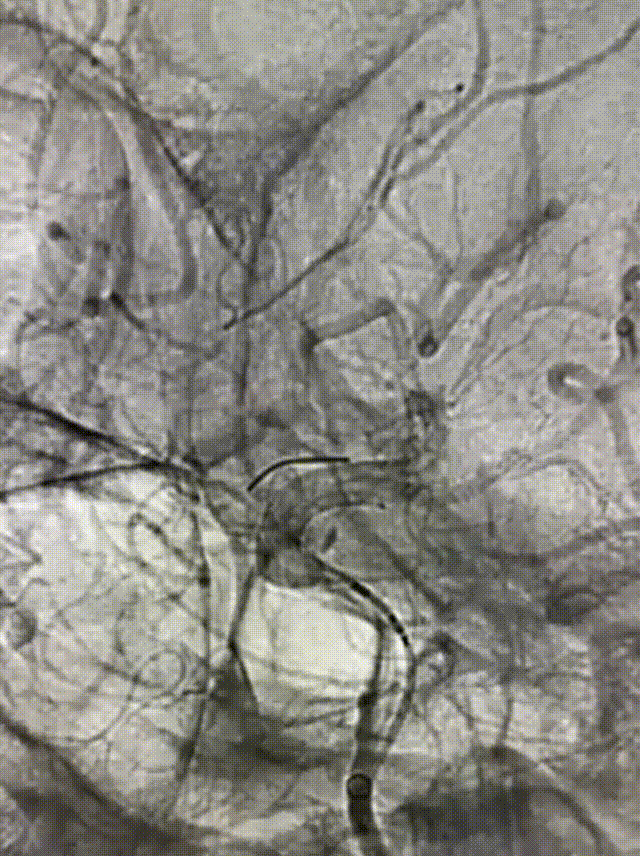

3D-DSA检查

术前造影测量血管直径及长度,选择合适的密网支架。

8F血鞘组、6F 90cm 长鞘、125cm多功能造影管、亲水涂层泥鳅导丝以及5F 115cm 颅内支持导管建立治疗通路,选择合适工作角度,微导丝引导0.027" 支架微导管到位。

根据测量血管直径大小及长度,将0.027" 支架微导管置于大脑中动脉,推拉结合,将通桥麒麟™血流导向密网支架 3.5*20mm头端释放,泄支架微导管张力后,将支架后撤至大脑前分叉处,逐步释放支架到一半定位,观察是否覆盖大脑前动脉分叉。

确定位置可,未覆盖前分叉处,支架位置及形态可,贴壁良好,半释放通桥麒麟™血流导向密网支架 。

通桥麒麟™血流导向密网支架完全释放后造影,支架贴壁良好,位置可。

通桥麒麟™血流导向密网支架完全释放后,微导丝塑型,成攀按摩支架,使支架贴壁更佳。

通桥麒麟™血流导向密网支架完全释放,造影示动脉瘤内造影剂滞留明显。

通桥麒麟™血流导向密网支架完全释放,全脑血管造影。